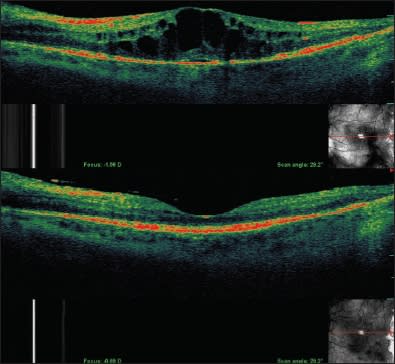

Another key measurement was change in central foveal thickness (Figure 2). OCT documented a mean decrease of 146 μm over the eight months of the study. All five patients experienced a reduction in central foveal thickness.13

Figure 2. Effect of intravitreal ranibizumab on radiation maculopathy. Top: Pretreatment OCT demonstrating significant radiation macular edema. Bottom: After six months of treatment, there is marked regression of macular edema and restoration of normal macular contour on OCT imaging.